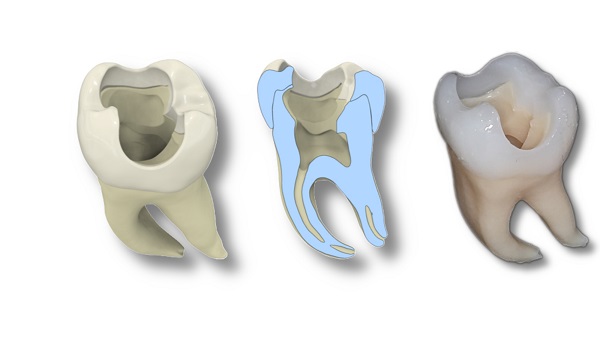

Bild 2: Konstruktion eines Übungszahnes basierend auf der Rekonstruktion eines echten Zahnes; v.l.n.r. Übersicht des ganzen Zahnes bestehend aus Schmelz und Dentin, Querschnitt des Zahnes, kompletter im 3D-Druckverfahren hergestellter Zahn. © Christian Höhne / UKW